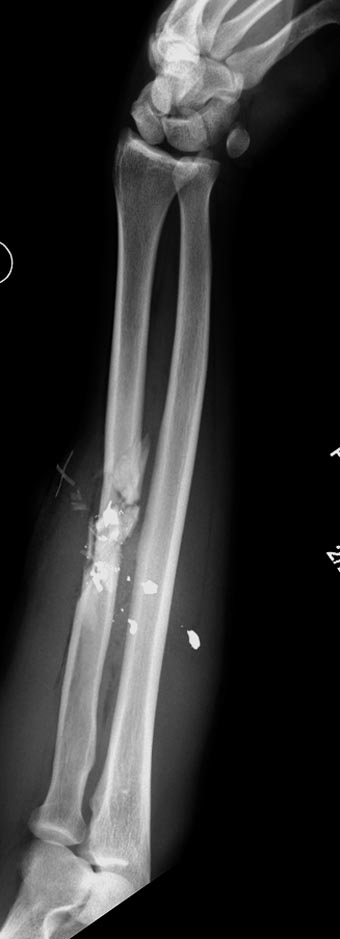

Здесь примеры: двоюродные братья с ранением предплечья, у одного

локтевая, а у второго лучевая. В следующее утро локтевая фиксирована без

обнажения фокуса травмы из небольших доступов, а второй из обычного

волярного доступа. А клинический снимок из прошлых операций...

Имя     : GSW radius 1.jpg

Тип     : image/jpeg

Размер  : 34919 байтов

Url     : http://weborto.net:8080/pipermail/ortho/attachments/20140728/123f732a/attachment-0010.jpg